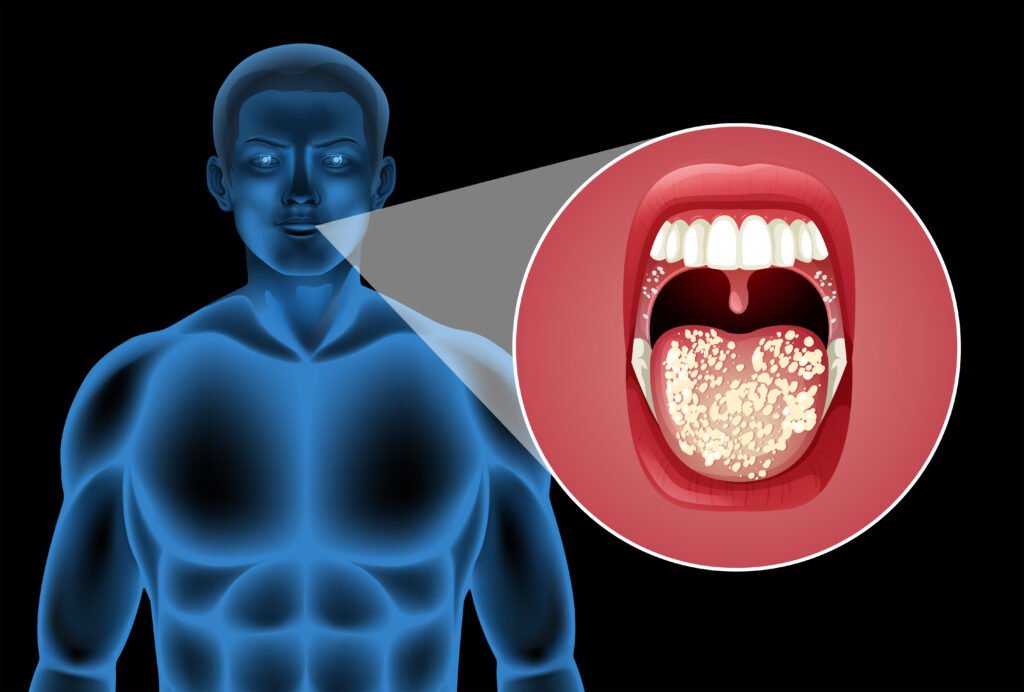

Oral hygiene refers to the actual process of maintaining a healthy mouth, teeth, and gums, free of dental diseases and other issues such as bad breath. Regular tooth brushing and interdental cleaning (cleaning between the teeth) are some of the key aspects of oral hygiene.

- Oral Microbiome: The ecosystem of microorganisms in the mouth plays a role in oral health. Body shifts of this balance can result in dental caries (cavities) and gum diseases like gingivitis and periodontitis.

There exist close and deep-rooted links between oral health and body health. It has been seen that oral infections particularly periodontal (gum) disease may have an impact or be associated with the onset and progression of many systemic diseases by various pathophysiological mechanisms. The following are the important aspects regarding this relationship:

- Periodontal Disease and Systemic Effects: Periodontal disease, which is a bacterial infection in the dental plaque, causes inflammation and degradation of gum tissue and bone, which support the teeth. Infections and inflammation of gums may transiently enter the bloodstream (transient bacteremia), distributing bacteria, microbial toxins, and inflammatory mediators to the body.